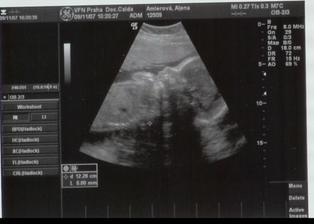

22.6.2007 první ultrazvuk -----

9.11.2007 jsme byly na biometrii a mame cca 952g -----